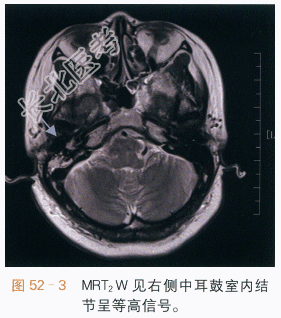

读片分析:面神经鞘瘤多见于面神经位于内耳与鼓室交界处的膝状神经节的面神经管内,它使面神经管扩大,CT扫描可见鼓室内沿后壁的软组织结节影及周围骨质的吸收或破坏,如图52-1所示,在MR图像上,面神经瘤呈等或等高信号,具轻度强化,如图52-2~图52-4所示,面神经鞘瘤主要的临床症状是面神经麻痹或面肌痉挛,可伴听力下降。由于患者临床症状出现较早,因此初次发现的面神经鞘瘤通常不大,需要我们仔细地进行影像学观察,否则容易遗漏。生长得比较大的面神经瘤,可以见到神经鞘瘤特有的囊实性结节,及其相应的影像学表现。